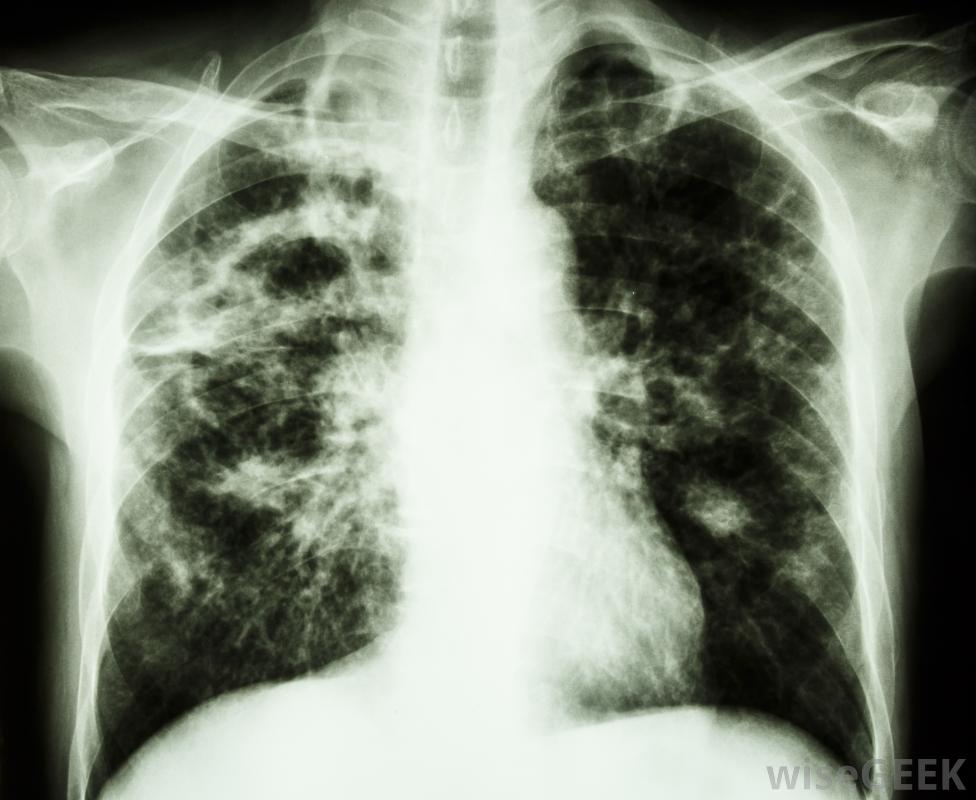

异烟肼是一种治疗肺结核的药物。它也可以用来预防那些接触过结核病感染者的人。这种抗生素的作用是抑制结核杆菌的生长和繁殖。因为它只能治疗活动性结核病感染,患有非活动性感染的人可能需要继续治疗长达一年。胃部的压痛或疼痛可能是异烟肼的副作用这种药物通常每天服用一次,喝满一杯水。除非会引起胃部不适,否则应该空腹服用。异烟肼可以是片剂或胶囊,吞咽困难的患者可以使用糖浆形式。通常,医生会在这种疗法的同时开一种B6维生素来抵消潜在的麻木或刺痛感。酸奶油会与异烟肼相互作用,因此应该避免。当一个人服用异烟肼时,应严格避免饮酒,因为它可能更容易造成肝脏损害。某些食物也必须避免或谨慎食用,如人参、巧克力,以及豆制品。熟肉、鸡肝和一些乳制品,如酸奶油和酸奶,也会与异烟肼相互作用鳄梨,香蕉,葡萄干,以及许多类型的奶酪,如马苏里拉奶酪,美式奶酪和切达奶酪都应该受到限制。所有的咖啡因,酸菜,食用无花果也应格外小心。异烟肼的副作用可能包括腺体肿胀服用异烟肼时食用这些食物可能会导致相互作用。这可能导致呕吐、恶心和腹泻。也可能发生胸痛、心跳不规则和潮红。一些患者报告严重头痛、潮红和颈部僵硬。如果患者出现这些症状,必须立即就医服用异烟肼的患者应定期进行血液检查,以确保肝脏功能正常患者还应注意异烟肼可能产生的其他副作用。这些副作用包括眼睛疼痛和其他视力问题、发烧、胃部压痛、皮疹、腺体肿大,可能会出现喉咙痛、四肢麻木或刺痛。出现这些症状的人应立即联系医生。异烟肼用于帮助清除活动性结核病感染异烟肼也可能与某些实验室检查相互作用,如尿糖试验。对乙酰氨基酚、抗真菌药物和苯妥英钠也可能与异烟肼相互作用。患者应在使用前与处方医生讨论所有其他药物和补充剂截至2011年,没有足够证据表明服用该药对未出生或哺乳期婴儿的潜在风险。如果患者怀孕,应立即通知医生。此外,患有肝脏或肾脏疾病、糖尿病或人类免疫缺陷病毒(HIV)的患者可能需要调整该药物的剂量。异烟肼的副作用可能包括严重头痛。